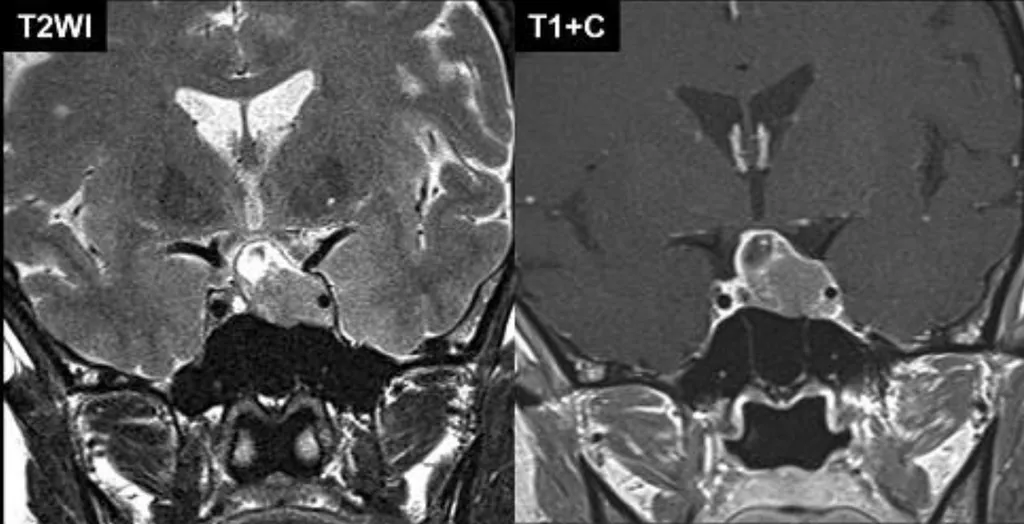

這題的解題核心在於辨識影像中腫瘤的「位置」與「顯影特性」,圖片顯示一個位於腦下垂體區域、顯影均勻的腫塊,這是腦下垂體腺瘤的典型表現。